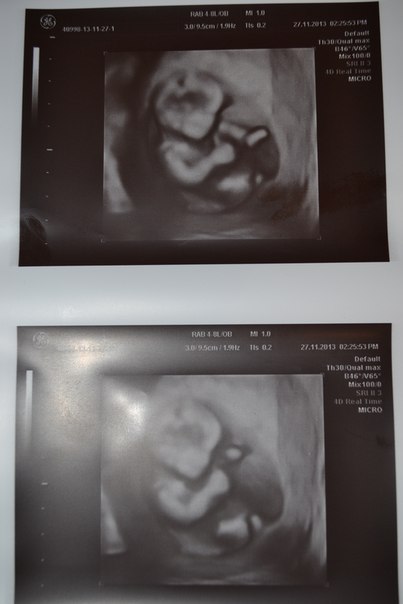

Анализы, скринингиСегодня мы с крошкой делали УЗИ и сдавали кровь.Я была на 7 небе от счастья когда увидела свою кроху,мы делали и обычное,и 3Д УЗИ.Она махала мне ручкой,крутилась,вертелась.Мы прям уже совсем большие 6,5 см.Какое же это счастье,по дороге домой ехала и плакала от радости.Еще один приятный момент,моей гематомы больше нет.Теперь осталось дождаться крови,сказали через пару дней будет готова.

Вот она-наша зайка.Уже прям куколка))